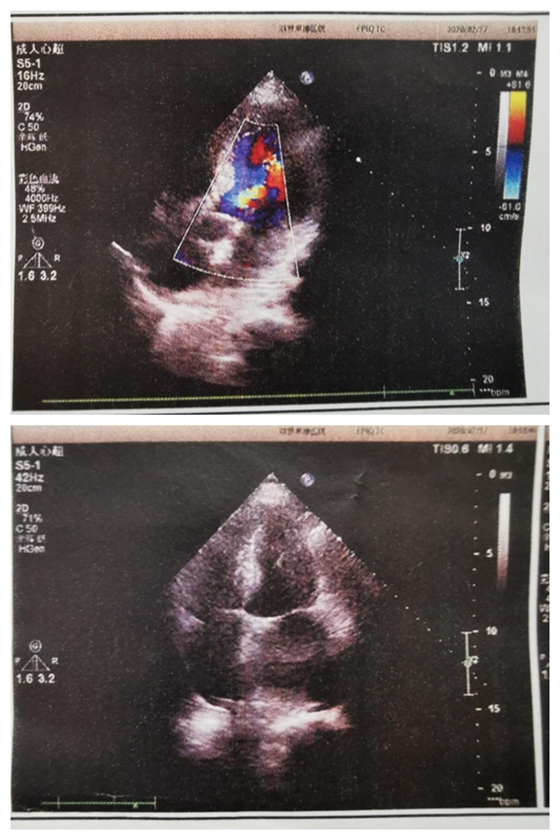

超声检查报告

超声检查结果